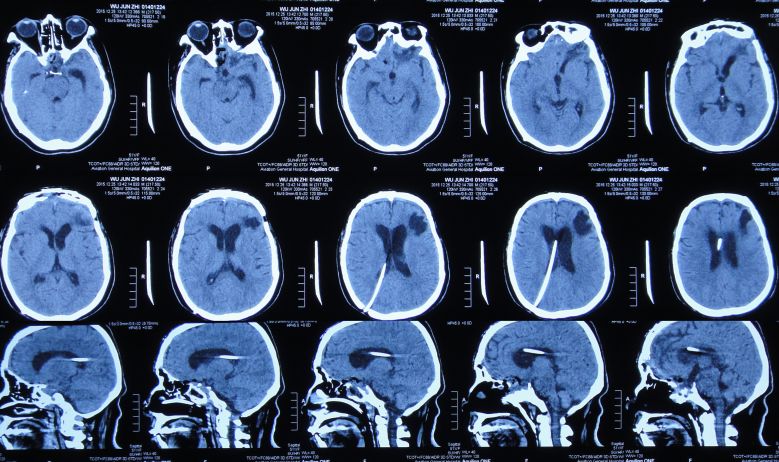

2015年7月27日患者突发高热,体温高达39.0 ℃,伴呕吐,意识转差,腰椎穿刺颅内压力极高,并留取脑脊液进行细菌培养;复查头CT检查显示脑室系统显著扩张,颅内积气(图11)。当日急诊进行了右侧侧脑室钻孔引流术,术后入住ICU给予重症监护、抗炎、抑酸等治疗。

图11:2015年7月27日头CT:脑室系统显著扩张,颅内积气